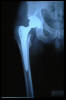

Fractura cuello fémur. Prótesis completa.